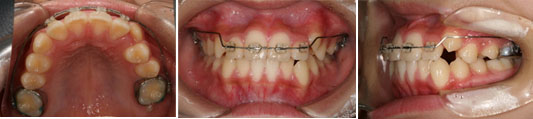

主訴:永久歯のスペースが不足している(叢生)

上下マルチブラケット使用

非抜歯

概算費用:75万円

初診時(10歳)

5か月後

1年5か月後

リスク副作用:歯根吸収、あと戻り